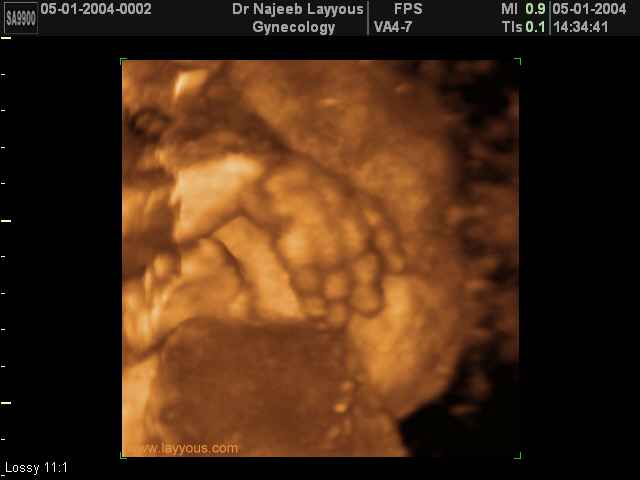

- 3D Fetal Limbs Ultrasound Scan Photos